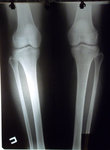

Дата операции 10.11.2014г.

Исходник.

SAM_9315.JPG